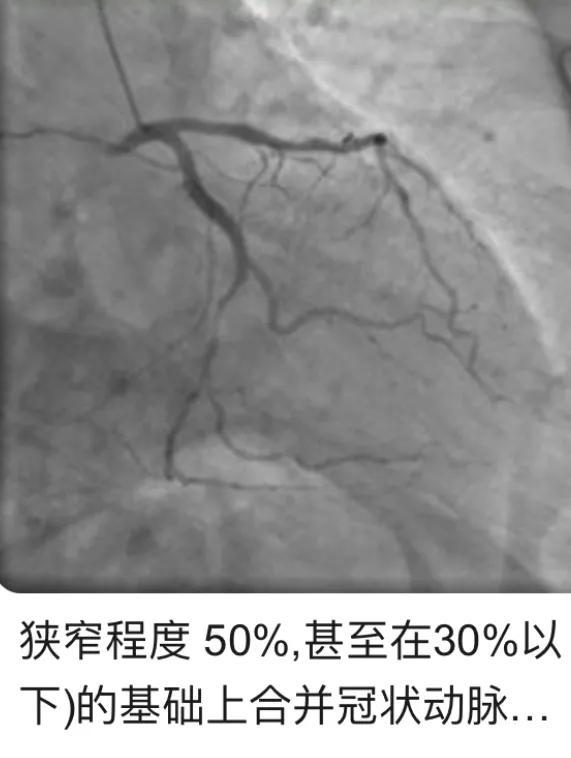

L'étalon-or pour le diagnostic de la maladie coronarienne : La maladie coronarienne peut être diagnostiquée par la coronarographie, qui révèle que la sténose de l'artère coronaire principale gauche ou d'une ou plusieurs branches descendantes antérieures gauches, de la branche circonflexe gauche ou de l'une des artères coronaires droites est supérieure à 50 pour cent.

Les résultats de la coronarographie concernant l'athérosclérose causée par une sténose inférieure à 50 % ne peuvent pas être qualifiés de maladie coronarienne, mais seulement de lésions athéroscléreuses des artères coronaires. Si la sténose de l'artère coronaire est supérieure à 50 %, le médecin généraliste vous prescrira des statines, si ces médicaments réduisent le cholestérol des lipoprotéines de basse densité LDL de plus de 50 %, mais pas seulement pour que la plaque ne soit plus une "croissance folle", pour qu'elle devienne plus stable et moins susceptible de se rompre et de déclencher un infarctus du myocarde, en raison des lipides centraux dans la plaque, le principal composant du LDL, le LDL, le principal composant du cholestérol des lipoprotéines de basse densité LDL. LDL, le principal composant des lipides de base dans les plaques, diminue de manière significative de plus de 50 % de sa valeur initiale, et peut même rendre les plaques plus petites et les inverser, si la sténose initiale n'est que légèrement supérieure à 50 %, en raison du rétrécissement de la plaque, la mécanisation fait que la sténose devient inférieure à 50 %, et alors le chapeau de la maladie coronarienne ne peut pas être mis sur la tête. Cette situation est encore souvent observée en clinique.